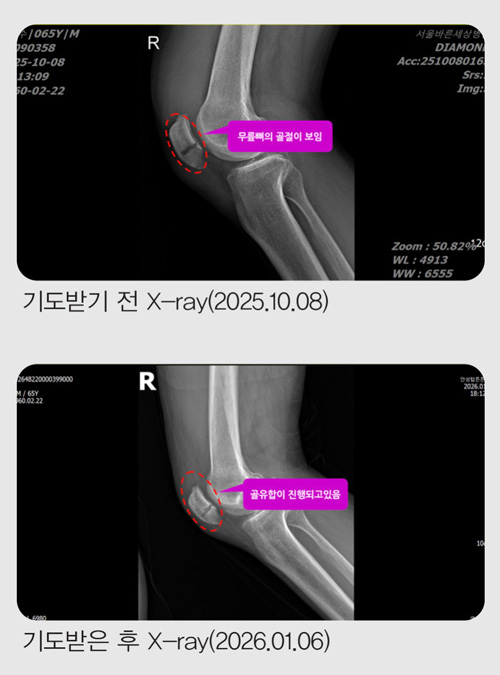

ÀÛ³â 10¿ù 8ÀÏ ¼ö¿äÀÏ, Ãß¼® ¿¬ÈÞ¸¦ ¸Â¾Æ ¸ðó·³ °¡Á·µé°ú ÇÔ²² ºÏÇѻ꿡 ¿Ã¶ú½À´Ï´Ù.

»êÇàÀ» ½ÃÀÛÇÑ Áö ¾à 15ºÐÂë Áö³µÀ» ¶§, »ÏÁ·ÇÏ°Ô Æ¢¾î³ª¿Â µ¹¸æÀÌ¿¡ ¿ÞÂÊ ¹ß¸ñÀÌ °É·Á ³Ñ¾îÁ³½À´Ï´Ù.

´Ù½Ã ÀϾ »êÀ» ¿À¸£·Á ÇßÁö¸¸ ¹«¸À» Â´Â µíÇÑ ±Ø½ÉÇÑ ÅëÁõ¿¡ ´õ ÀÌ»ó ÇÑ ¹ß¦µµ ¿òÁ÷ÀÏ ¼ö ¾ø¾î °á±¹ »êÀ» ³»·Á¿Í¾ß Çß½À´Ï´Ù. ³»·Á¿À´Â ±æÀº »êÇຸ´Ù ÈξÀ ´õ °íÅ뽺·¯¿ü½À´Ï´Ù. µÎ ¼ÕÀ» ¹Ù´Ú¿¡ ¤°í °è´ÜÀ» ÇÑ °è´Ü¾¿, ÇÑ ¹ß·Î °£½ÅÈ÷ ³»·Á¿Í °Ü¿ì Åýÿ¡ ¸öÀ» ½ÇÀ» ¼ö ÀÖ¾ú½À´Ï´Ù.

Åýà ¾È¿¡¼ ¹«¸À» ¸¸Áö´Â ¼ø°£, »À°¡ ºÎ·¯Á³´Ù´Â °ÍÀÌ ºÐ¸íÈ÷ ´À²¸Á³½À´Ï´Ù.

Áý ¾Õ¿¡ µµÂøÇßÁö¸¸ ÇÑ ¹ß¦µµ °È±â Èûµé¾î ´Ù½Ã Åýø¦ Ÿ°í ±Ùó °³ÀÎ º´¿øÀ¸·Î °¬°í, °ð¹Ù·Î Å« º´¿ø ÀÀ±Þ½Ç·Î À̵¿Ç϶ó´Â ¸»À» µé¾ú½À´Ï´Ù.

ÀÀ±Þ½Ç¿¡¼ MRI¸¦ ÃÔ¿µÇÑ µÚ, ÀÇ»ç ¼±»ý´ÔÀº "¹«¸»À°¡ °ñÀýµÆ½À´Ï´Ù. ¹«¸Àº ÀÏ¹Ý »À¿Í ´Þ¸® À§¾Æ·¡°¡ ºÐ¸®µÅ ÀÖ¾î ¹Ýµå½Ã ¼ö¼úÀÌ ÇÊ¿äÇÕ´Ï´Ù"¶ó°í ¸»Çß½À´Ï´Ù.

ÀÌ¾î ¼ö¼úÀ» ÇÏ´õ¶óµµ ¸ñ¹ß »ç¿ë°ú ÀçȰ Ä¡·á°¡ ÇÊ¿äÇÏ´Ï 10¿ù 10ÀÏ ±Ý¿äÀÏ¿¡ ¼ö¼úÀ» ÇÏÀÚ°í ±ÇÇß½À´Ï´Ù.

±×·¯³ª ÀÔ¿øÇØ ¼ö¼úÀ» ¹Þ°Ô µÇ¸é 10¿ù 12ÀÏ¿¡ ÀÖ´Â ±³È¸ ⸳ 43Áֳ⠱â³ä ¿¹¹è¿¡ Âü¼®ÇÒ ¼ö ¾ø¾ú½À´Ï´Ù. Àú´Â ¹ÏÀ½À¸·Î Ä¡·á¹Þ°íÀÚ ÀÔ¿øÀ» ¼±ÅÃÇÏÁö ¾Ê°í ÁýÀ¸·Î µ¹¾Æ¿Ô½À´Ï´Ù.

10¿ù 14ÀÏ, °ñÀýµÈ Áö 6ÀÏ ¸¸¿¡ Á¤Çü¿Ü°ú¸¦ ã¾Æ X-ray¸¦ Âï¾ú½À´Ï´Ù.

ÀÇ»ç´Â "»À°¡ °ÅÀÇ ´Ù Àß ºÙ¾ú½À´Ï´Ù. ÀÌÁ¦ °ü¸®¸¸ ÀßÇÏ½Ã¸é µË´Ï´Ù"¶ó°í ¸»Çß½À´Ï´Ù.

ÀÏ¹Ý »Àº¸´Ù Ä¡·á°¡ ±î´Ù·Î¿î ¹«¸»À°¡ ºÒ°ú ¸çÄ¥ ¸¸¿¡ ºÙÀº °ÍÀÔ´Ï´Ù. ÇÒ·¼·ç¾ß!